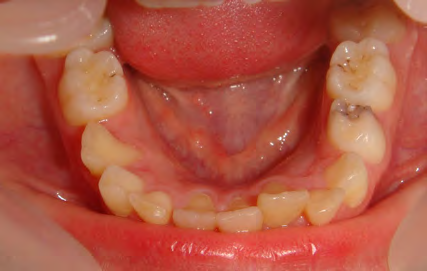

Below are cases treated at Vakresmil without extractions within the last three years. The families had been told, “It is simply not possible for your child to be treated without extractions” by orthodontists. Judge for yourself if that was right or wrong.

The overall aim is to produce the best smile we can — a “beautiful smile”, if you will — without premolar extractions, headgear, facemasks or banded appliances. A smile that both the patient and we at Vakresmil can be proud of.